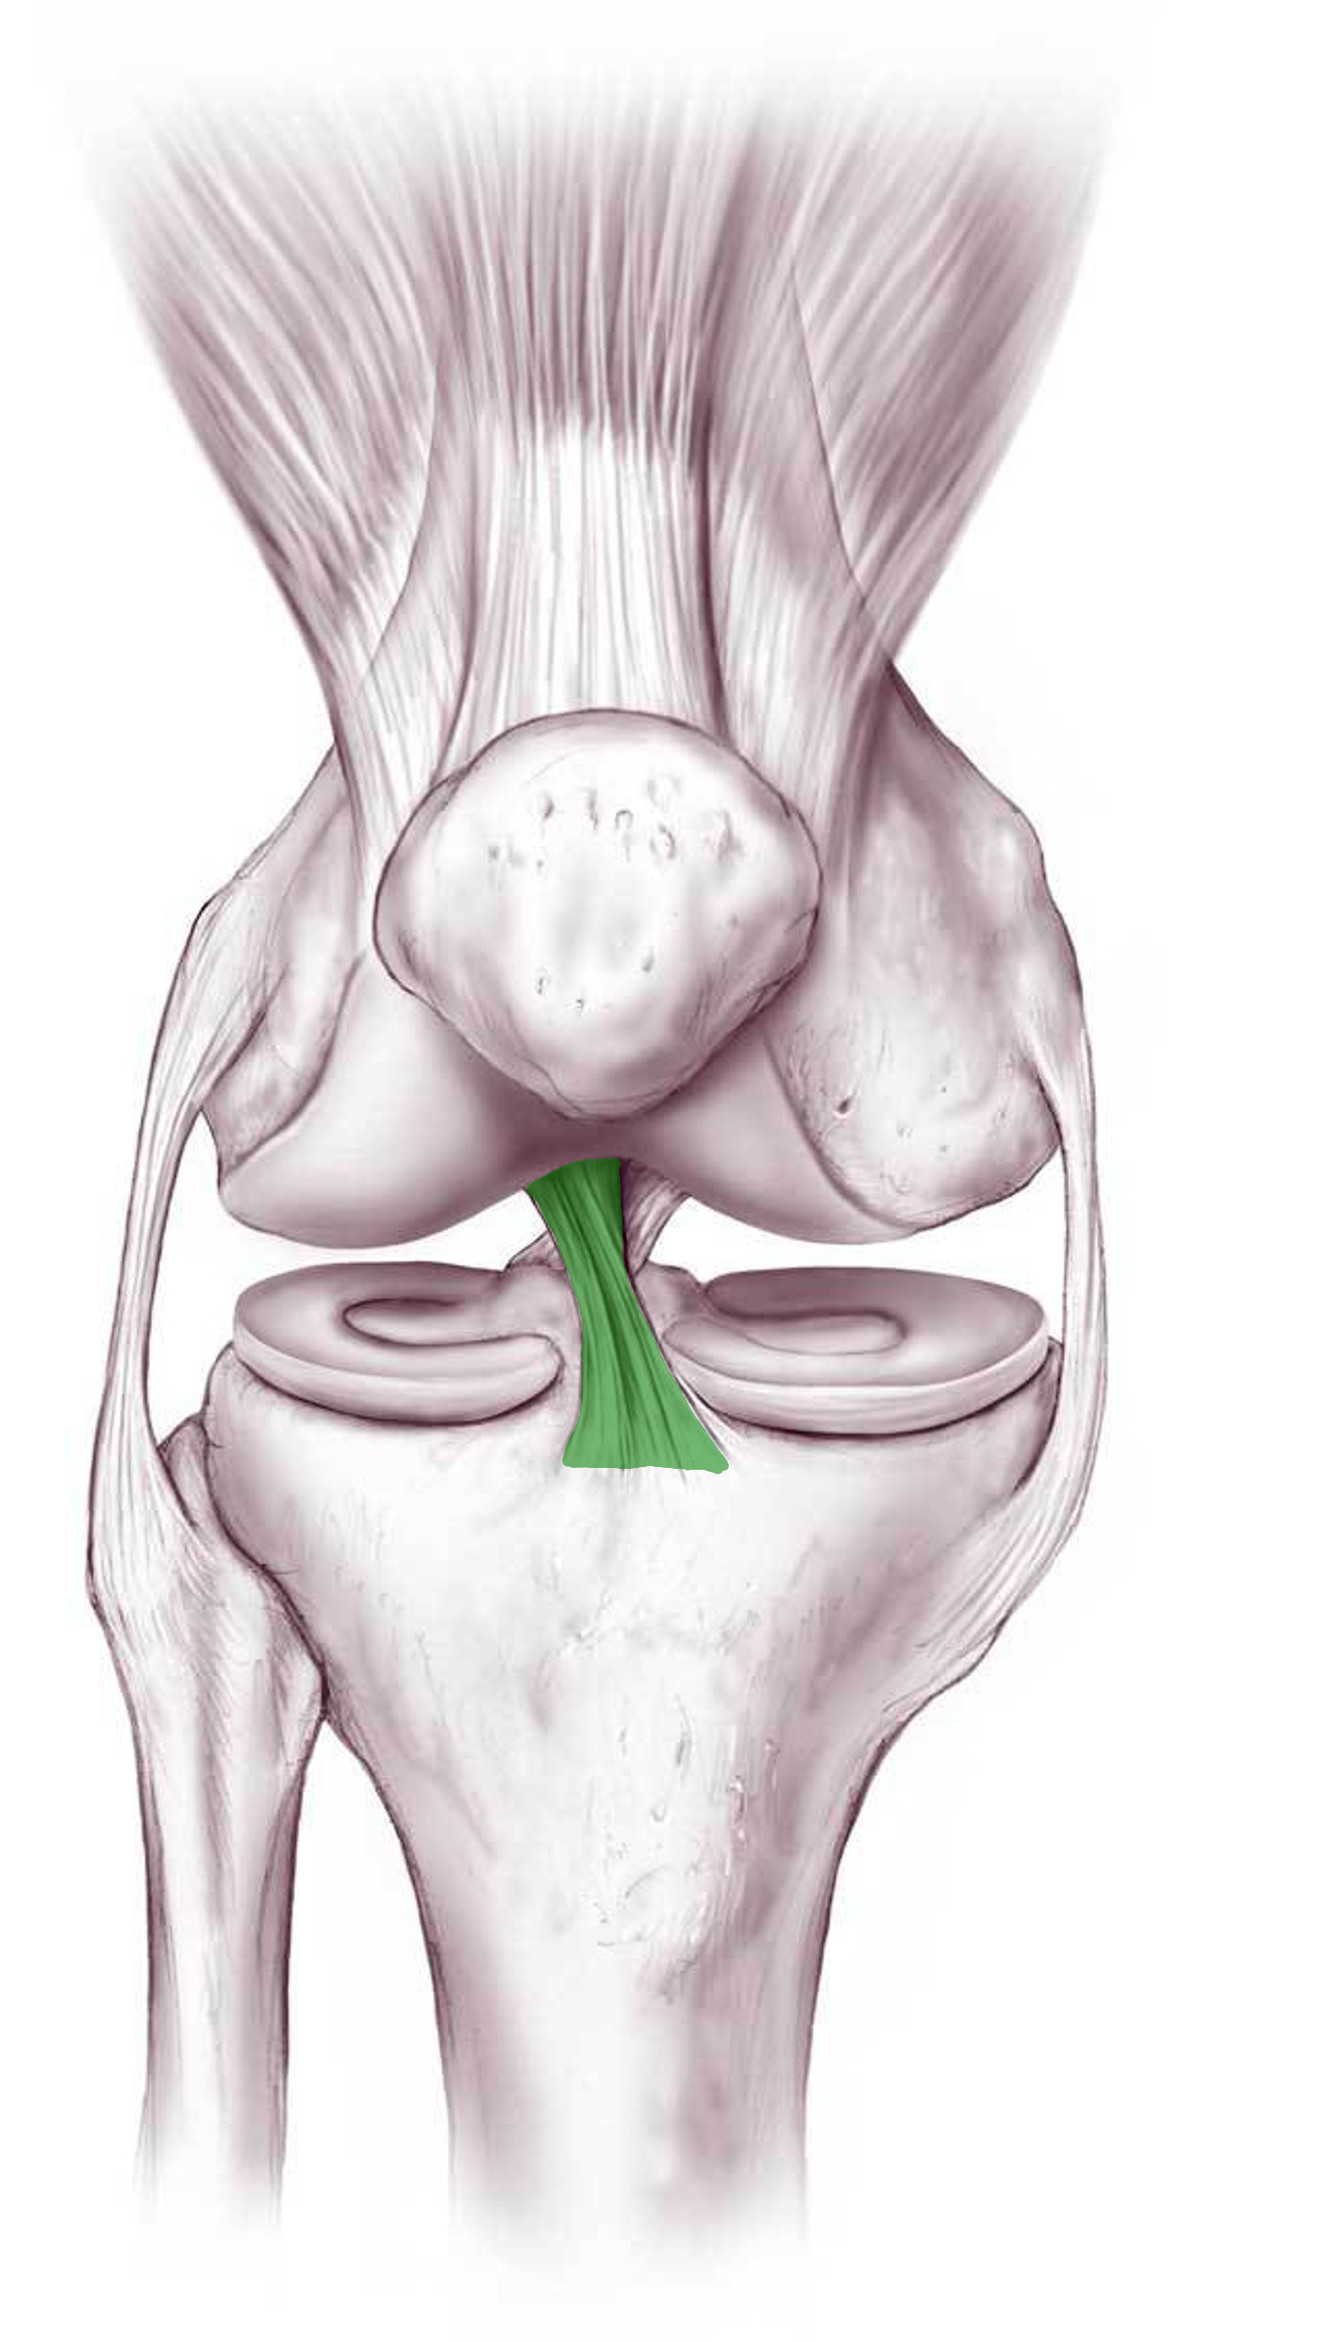

What is this structure?

Anterior cruciate ligament of the knee

What is the function of this structure?

Anterior cruciate ligament of the knee

Stops anterior dislocation of knee